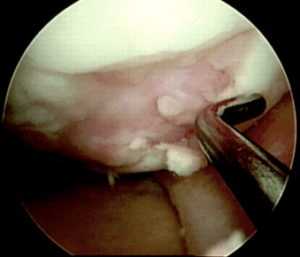

Далее осуществляется артроскопический доступ к мыщелку бедренной кости с поврежденным участком хряща. Производится очистка участка кюреткой и иссечение краев для получения ровного здорового контура. Затем вводится зонд с метками — с его помощью измеряют точный размер дефекта. Если дефект слишком большой или расположен очень далеко, операцию делают с помощью артротомии (открытым доступом).